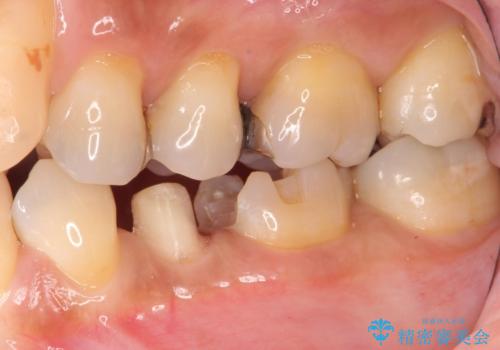

- 左下の奥歯に虫歯がある気がするとのことで来院された患者様です。

手前はジルコニアクラウンで白く、奥はゴールドアンレーでより適合の良いものを装着します。

銀歯の裏側に虫歯が確認されました。

小さな段差も虫歯のリスクにつながります。

精度の良い補綴物を入れることで今後の虫歯リスクを抑えることができます。